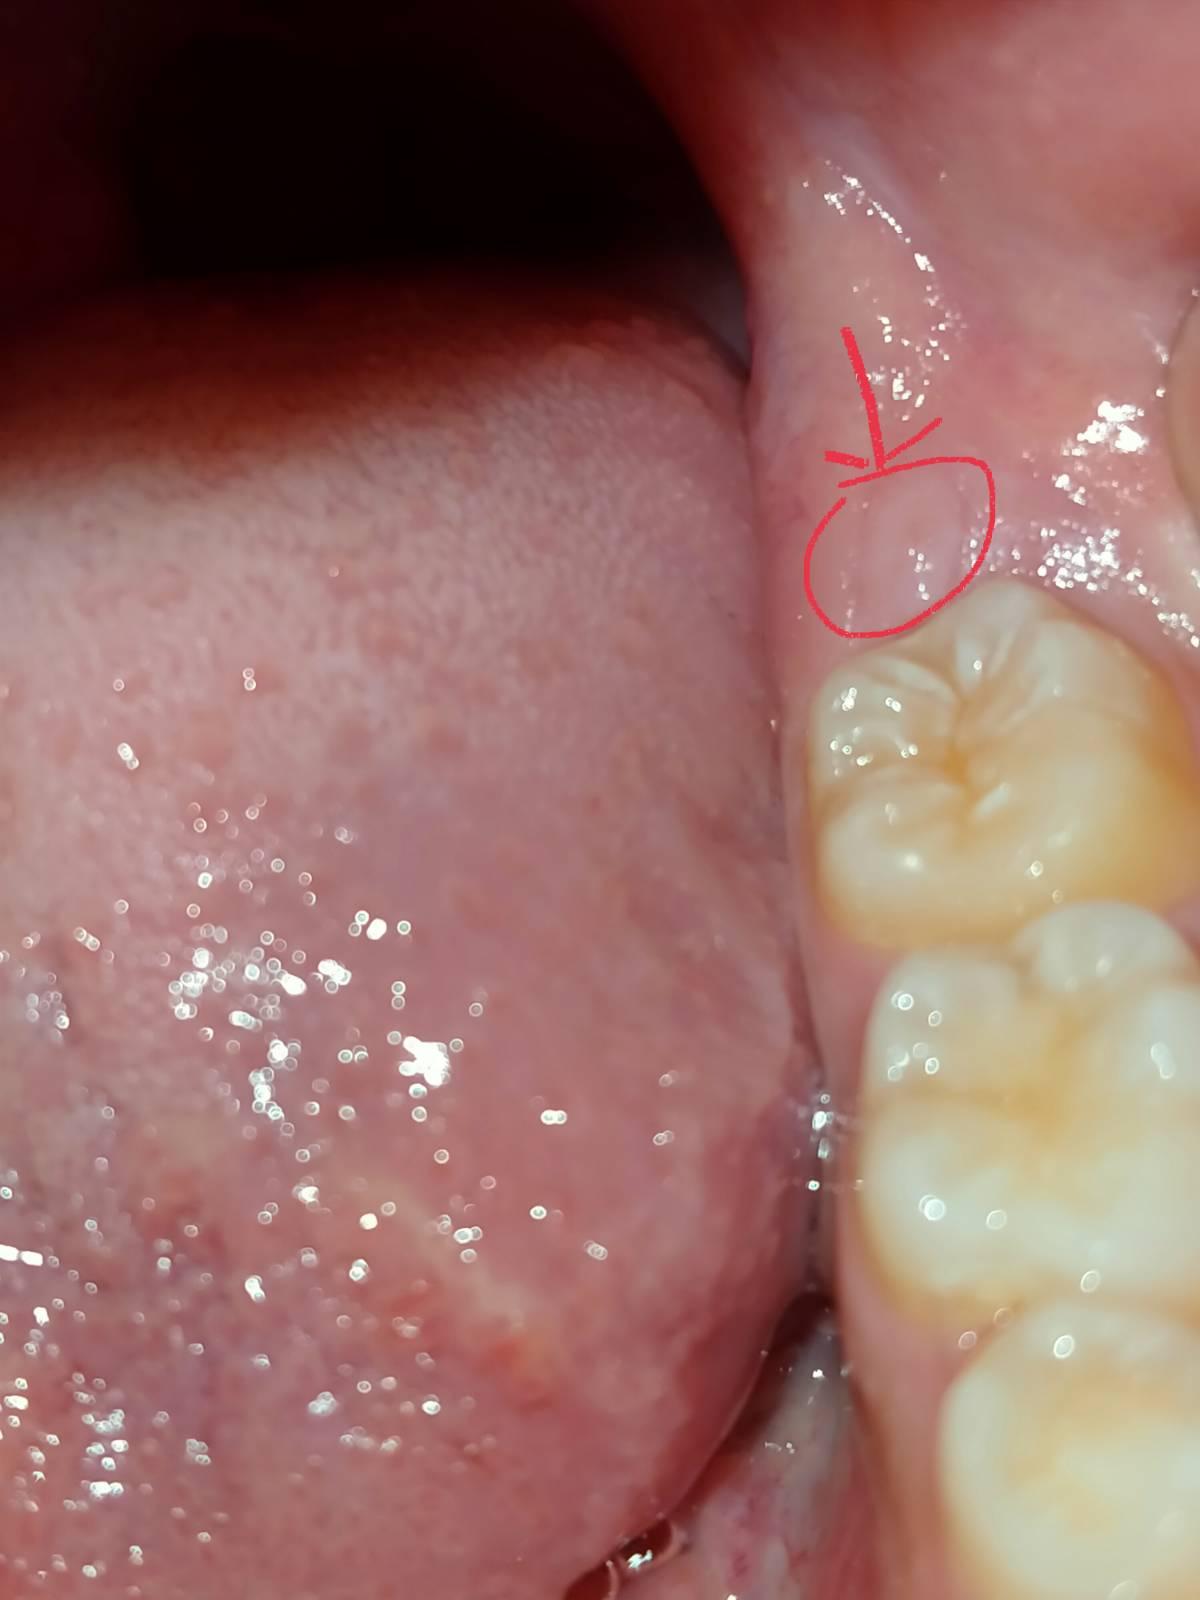

ในภาพมันคืออะไรครับ

ตามภาพเลยครับ มันคือฟันคุด หรือเนื้องอกครับ